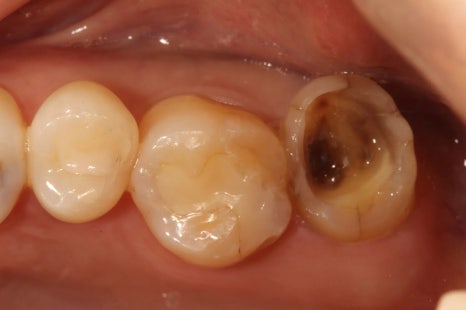

제 어금니 미니쉬 전후예요.

저는 오랫동안 이를 갈고 꽉 깨무는 습관이 있었어요.

게다가 치열 특성상 '나비치아'와 어금니 쪽 부정교합도 좀 있었고요.

그러다 보니 밥을 먹을 때마다 치아가 서로 갈리는 소리가 날 정도로 어금니가 정말 심하게 마모되었답니다.

어금니가 점점 닳아 없어지니 교합이 무너지고, 그 힘이 앞니로 전달되면서 앞니가 쓰러지듯 기울어지기 시작했어요.

그래서 저는 어금니를 복구하기로 했고 총 4개의 어금니 미니쉬를 받았어요.

마모가 심했던 어금니

오래된 인레이가 깨진 어금니 재치료

레진치료 후 이차 충치가 있던 어금니